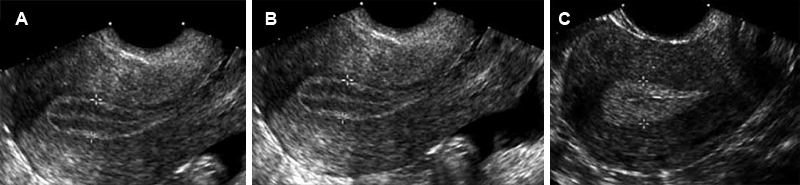

La THMcc causa un endometrio hipotrófico, delgado en la ultrasonografía (Figura 1A).

La THMsec determina un endometrio que difiere en la fase de E solos que en la fase estrógeno-progestativa (similar a lo que ocurre en los ciclos menstruales espontáneos) (Figura 1). Por ello, cuando el esquema de TH es secuencial, debe realizarse el ultrasonido en la fase de estrógenos solos, en que el endometrio debe presentarse como lineal (Figura 1A) o trilaminar (endometrio tipo 1) (Figura 1B). Si en esta fase de estrógenos solos, el endometrio se presenta heterogéneo, con focos de engrosamiento, u homogéneo de tipo 3 (como se observa en la fase progestativa de un ciclo espontáneo o farmacológico) (Figura 1C), debe entonces estudiarse el endometrio.

Figura 1. Ultrasonido en las diferentes fases del ciclo menstrual. A: endometrio lineal o hipotrófico. B: endometrio trilaminar – fase folicular del ciclo. C: endometrio homogéneo – fase lútea del ciclo.